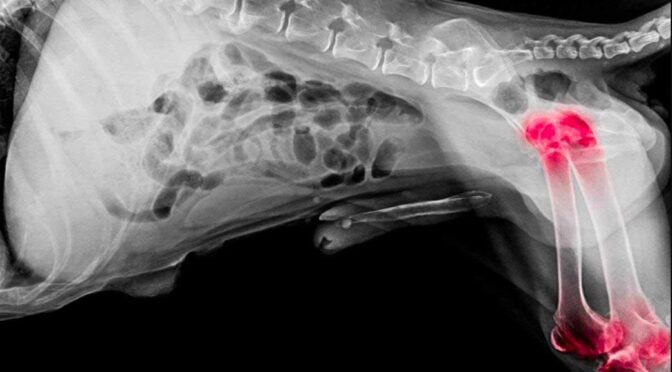

2. X-Rays (Radiographs): Bone cancer often shows a distinct pattern of bone destruction and irregular growth.

6. Chest X-Rays: Performed to check for metastasis in the lungs.

Veterinarians confirm it through imaging tests such as X-rays or CT scans, followed by a bone biopsy for definitive diagnosis.